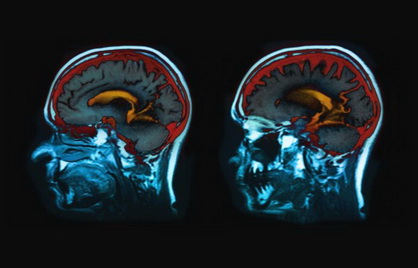

πAu Royaume-Uni, des recherches préliminaires réalisées sur plusieurs centaines d’IRM passées par des malades du Covid-19 suggèrent que le virus pourrait être responsable d’une atrophie de la matière grise du cerveau. Les conséquences du Covid-19 à long terme se dessinent. Alors que plus de 5% des malades souffrent d’un Covid long qui se manifeste par un prolongement des symptômes, une étude britannique montre que le virus pourrait aussi altérer le cerveau des malades. En analysant plusieurs centaines d’IRM cérébrales de patients ayant contracté le Covid-19, les scientifiques ont noté une atrophie de la matière grise du cerveau, habituellement observée au cours du vieillissement. Ces observations ont été faites même chez des personnes n’ayant pas développé de forme grave de la maladie. Pour réaliser cette étude, parue en août 2021, les scientifiques se sont appuyés sur une base de données britannique (BioBank) contenant les données d’imagerie cérébrale de plus de 45 000 personnes depuis 2014. L’équipe a analysé ces IRM avant de les comparer à ceux des patients qui avaient été testés positifs au Covid-19 en tenant compte de l’âge, du sexe, de la date du test de référence et du lieu de l’étude, ainsi que des facteurs de risque communs de maladie et le statut socio-économique.